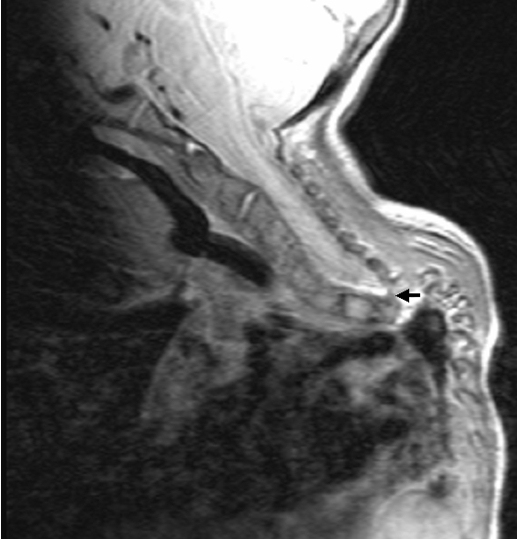

We referred to CT scanning to further localise the osseous malformation complex. Axial reformatted CT scan of C3 showed hypoplasia of the vertebral body associated with defective ossification of the pedicle, lamina and the spinous process respectively (Figure 2 [Fig. 2]). Sagittal reformatted CT scan showed occipitalisation of the anterior arch of the atlas, anterior and horizontal atlantoaxial dislocation associated hypoplasia of the vertebral bodies (Figure 3 [Fig. 3]). 3 D reconstructions CT scan showed significant disconnection of the posterior spine elements (arrow) related to underdeveloped pedicles and hypoplasia of the laminae along different cervical levels C2/4 and C6 associated with extensive malsegmentation (Figure 4 [Fig. 4]). Sagittal MRI showed the atrophic spinal cord at C7/T1 (in this patient there was a constellation of spinal osseous maldevelopment of the cervico-thoracic vertebrae with subsequent development of traumatic atrophy of the spinal cord) (Figure 5 [Fig. 5]).